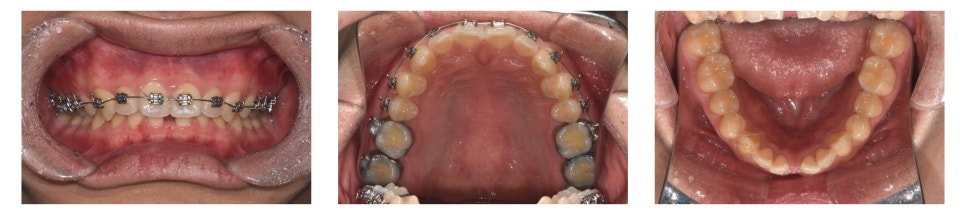

초진 구내 사진을 보면,

▶ 아래 앞니 사이가 많이 벌어진 상태(spacing)

▶ 앞니가 깊게 물려 있는 상태(deep bite)

를 확인할 수 있었습니다.

치료 시작 약 1년 후 모습입니다.

하악 중절치 사이의 공간(spacing)이 거의 닫혔고, deep bite 역시 많이 개선된 모습을 볼 수 있습니다.